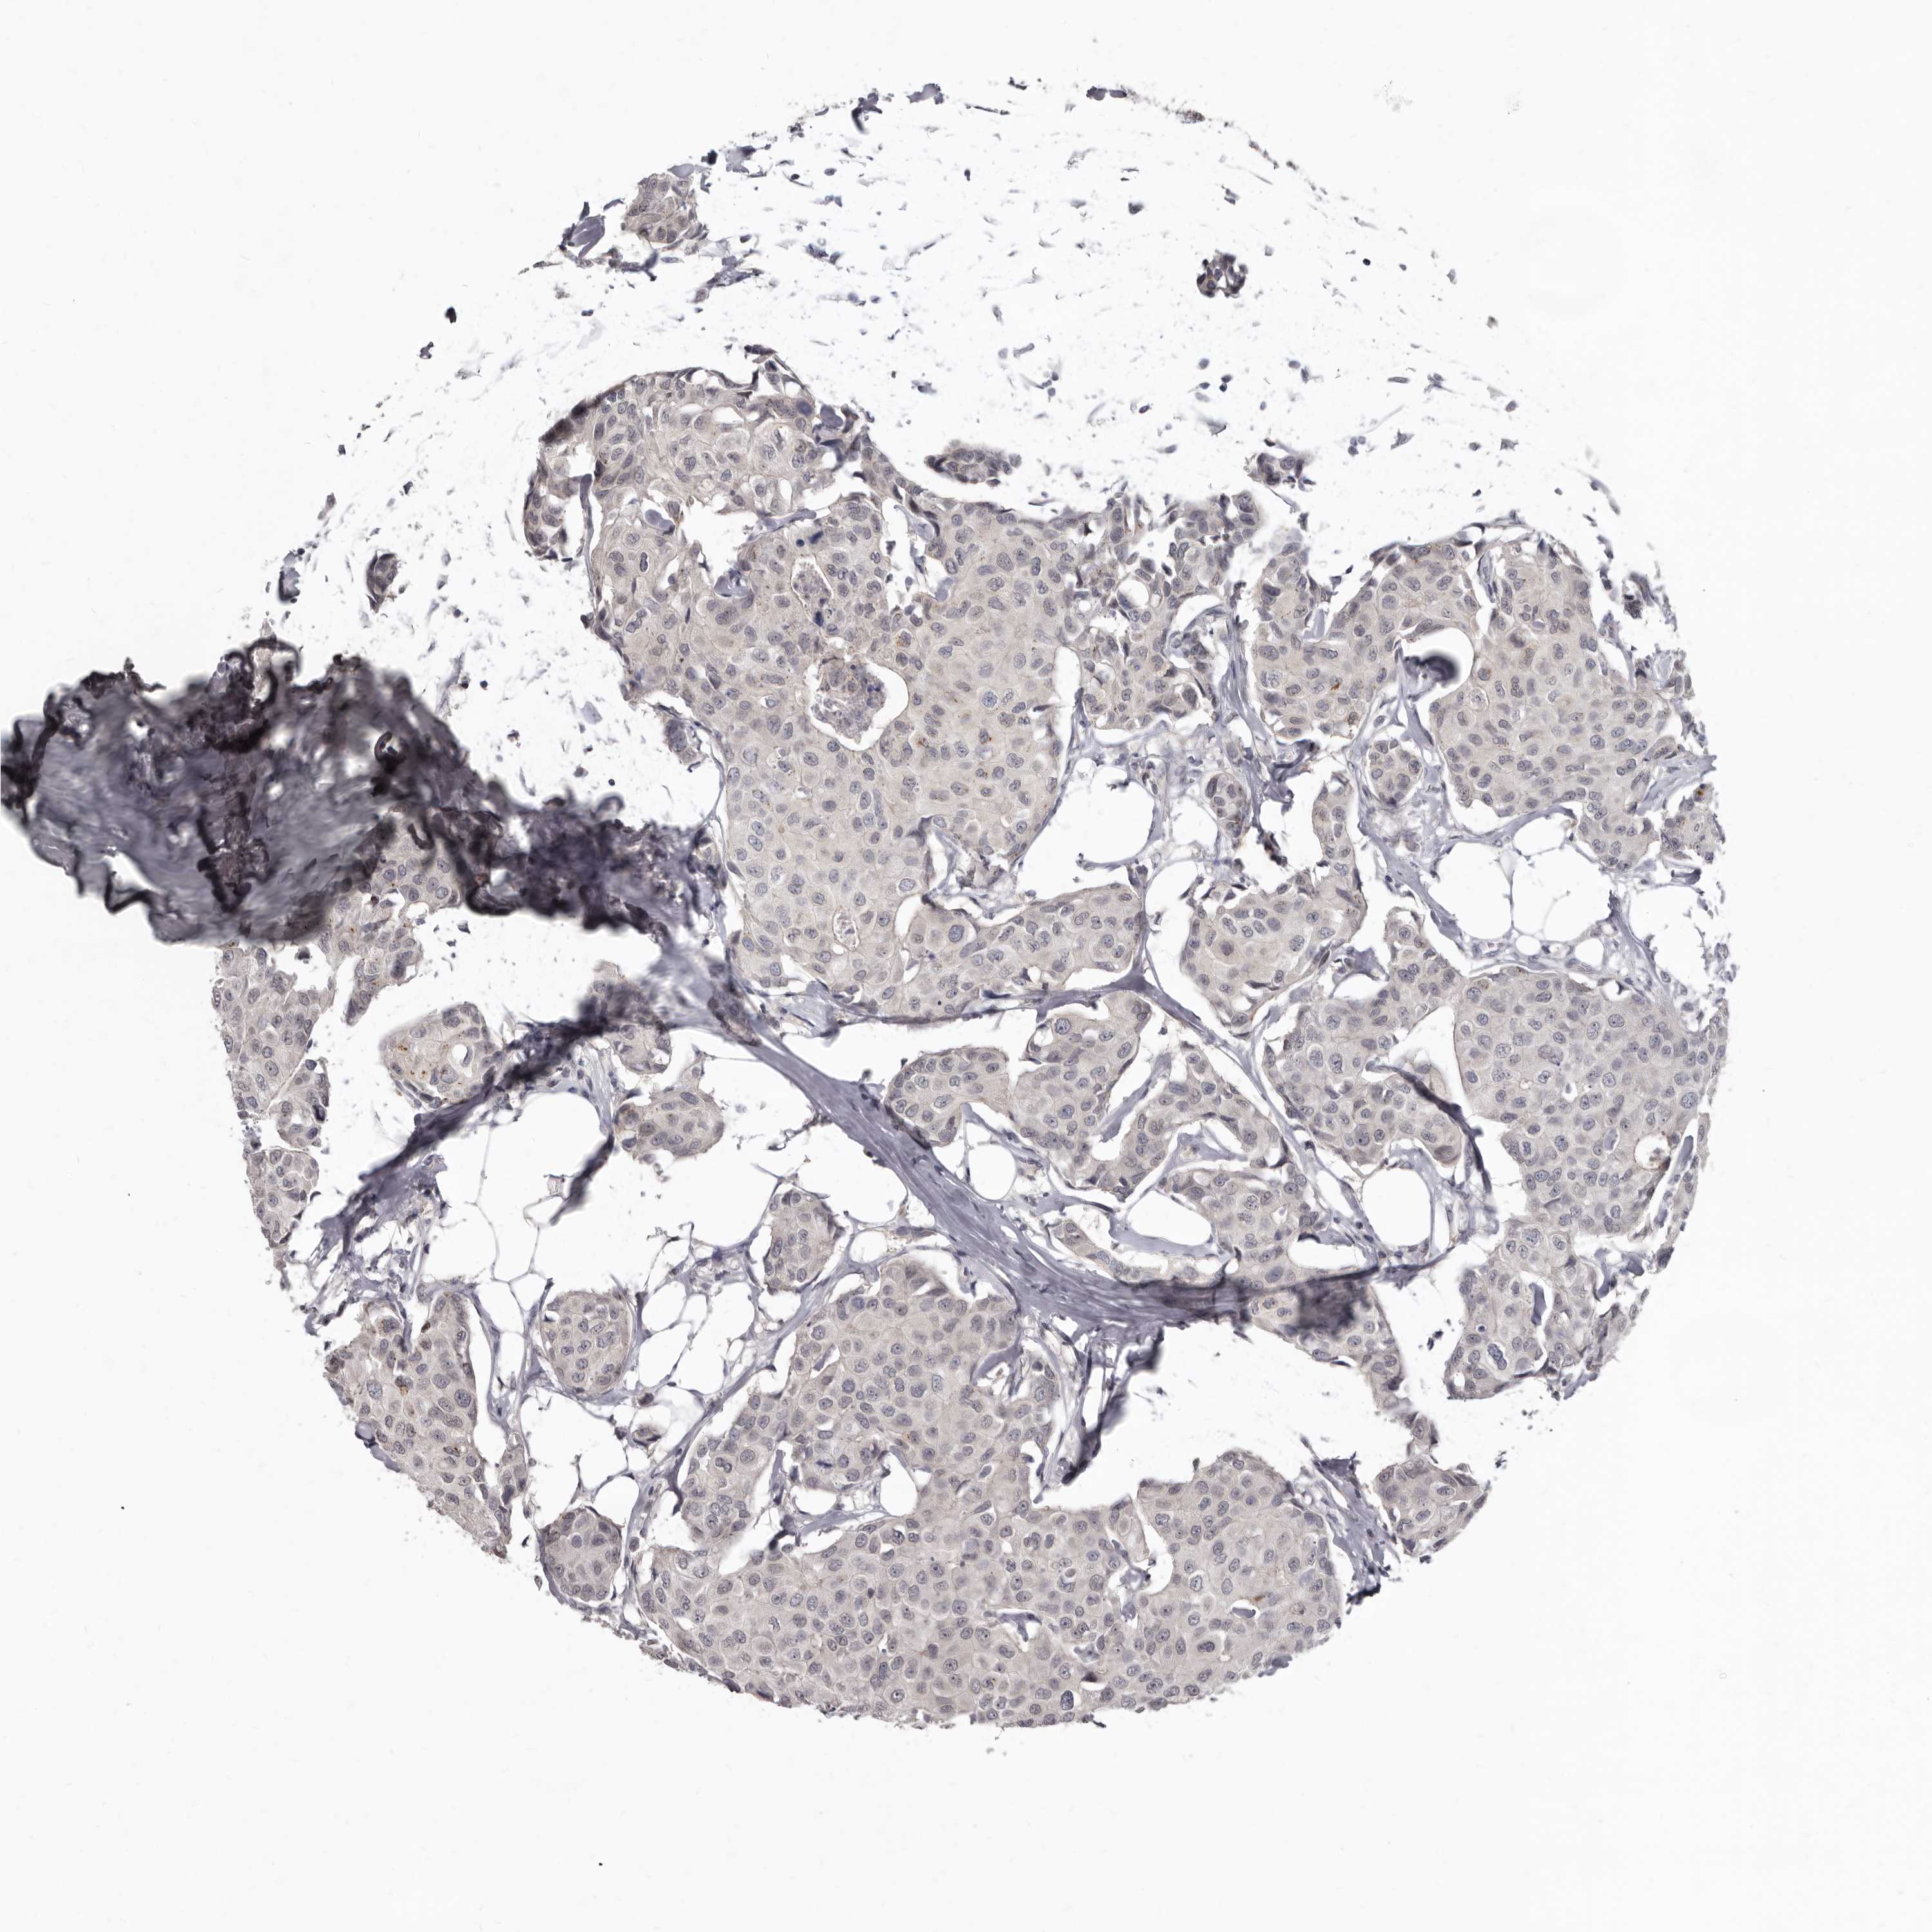

BRCA TCGA BRCA VALIDATION PROTEIN EXPRESSION